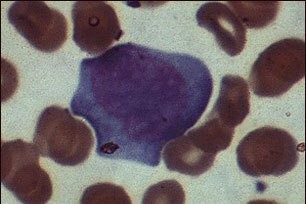

Эта, так называемая, "Ложная клетка", встречающаяся при инфекционном мононуклеозе, является типичным лимфоцитом, инфицированным ВЭБ (вирусом Эпштейна-Барра) или ЦМВ (цитомегаловирусом). При мононуклеозе можно выделить три морфологических типа лимфоцитов. Этот лимфоцит относится ко II типу клеток.